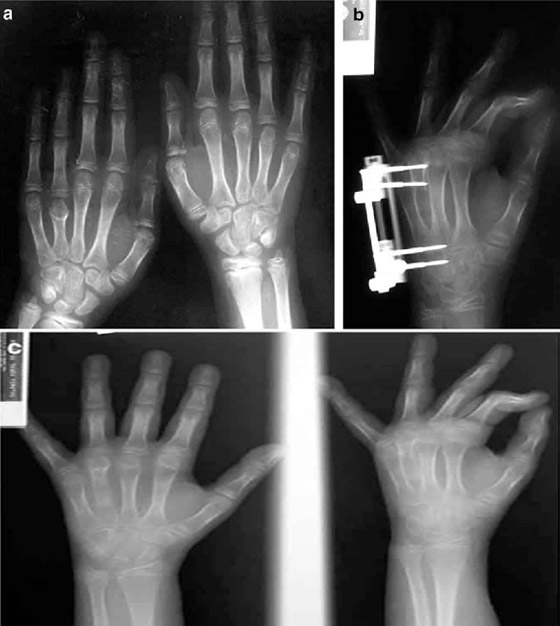

4. تكوين العظم السحبي أو "سحب الدشبذ": قد يلجأ الأشخاص الذين يعانون من تشوهات هيكلية كالأطراف متفاوتة الطول إلى ارتداء أحذية بكعوب متفاوتة. ولكن قد يكون هناك حل آخر لهذه الحالة الطبية وهي كسر الساق! تسمى هذه العملية بـ"تكوين العظم السحبي" أو "سحب الدشبذ"، والتي ابتكرها جراح العظام السوفييتي (غافرييل إليزاروف) في فترة الخمسينيات من القرن الماضي، حيث يتم كسر القشرة الخارجية للعظم، ثم يتم المباعدة تدريجياً بين طرفي العظم المكسور اصطناعياً باستخدام دعامات معدنية. بعد ذلك، يتشكل نسيج عظمي لملء التجويف بين العظمين المتباعدين. يمكن للطبيب تعديل الدعامات المعدنية بشكل مستمر إلى أن يصل العظم إلى الطول المطلوب. عادةً ما يلجأ الطبيب لهذا الإجراء لتصحيح العيوب الخلقية العظمية، أو لزيادة طول الشخص بضعة سنتمترات.